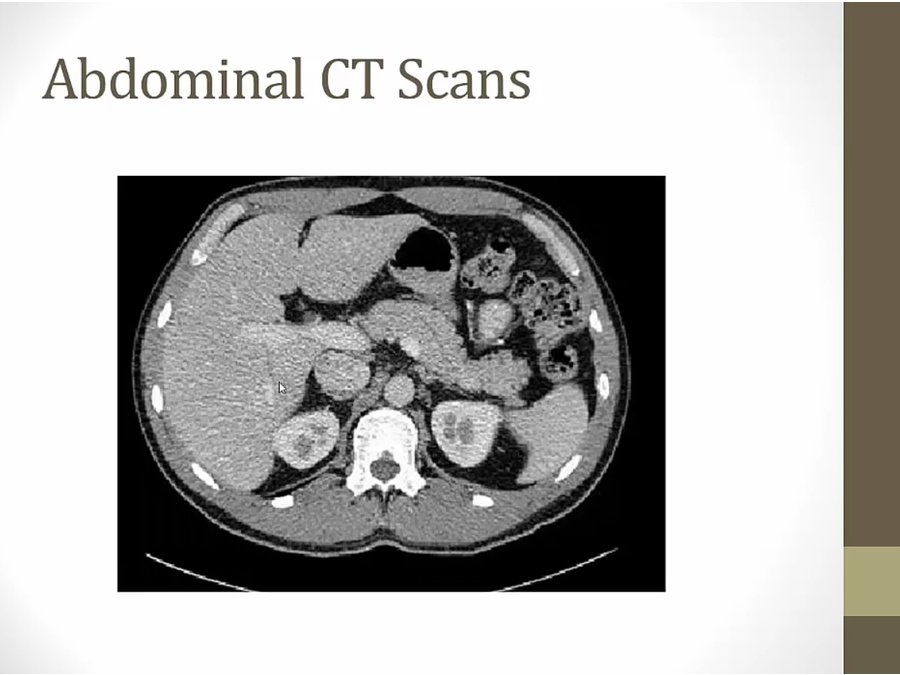

lower

portal vein diving into liver

stomach with air

intestines next to stomach